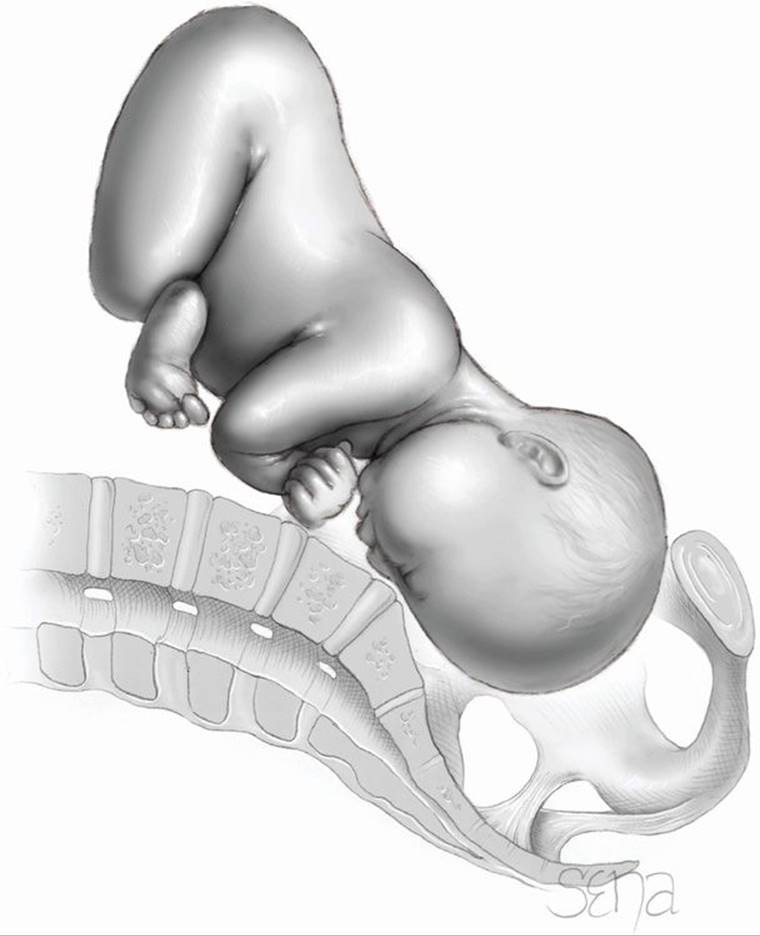

Fetal Dimensions in Fetopelvic Disproportion

Fetal size alone is seldom a suitable explanation for failed labor. Even with the evolution of current technology, a fetal size threshold to predict fetopelvic disproportion is still elusive. Most cases of disproportion arise in fetuses whose weight is well within the range of the general obstetrical population. As shown in Figure 23-5, two thirds of neonates who required cesarean delivery after failed forceps delivery weighed less than 3700 g. Thus, other factors—for example, malposition of the head—obstruct fetal passage through the birth canal. These include asynclitism, occiput posterior position, and face and brow presentations.

FIGURE 23-5 Birthweight distribution of 362 newborns born by cesarean delivery at Parkland Hospital (1989–1999) after a failed forceps attempt. Only 12 percent (n = 44) of the newborns weighed > 4000 g (dark bars).